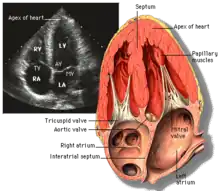

Transthoracic echocardiography (TTE)

Apical four chamber ultrasound view of heart

Transthoracic echocardiography (TTE) uses ultrasonic waves for continuous heart chamber and blood movement visualization. It is the most commonly used imaging tool for diagnosing heart problems, as it allows non-invasive visualization of the heart and the blood flow through the heart, using a technique known as Doppler.

TTE is commonly used to evaluate patients with coronary artery disease.[4] Stress echocardiography is used to diagnose coronary artery disease and assess myocardial viability.[4]